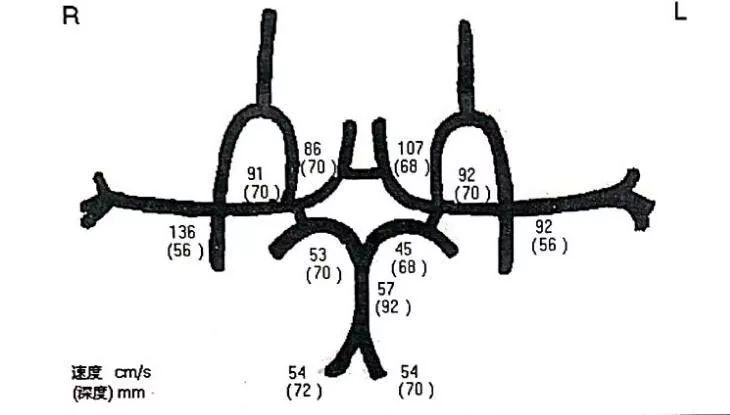

↑↑↑TCCD提示:同侧颈内动脉颅内段、大脑中动脉无狭窄。

图6:复查造影时行TCD检查

图9:术后第二天复查TCCD